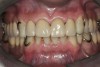

The framework was evaluated intraorally for fit, occlusion, retention, and stability (Figure 13, Figure 14 and Figure 15). With the framework in position, a new maxillo–mandibular relationship record was made with a silicone-based interocclusal record material, and the definitive casts were remounted on the articulator. The framework was returned to the laboratory, and acrylic resin veneers were applied in the esthetic zone and posterior artificial acrylic resin teeth were placed on the framework. The artificial teeth were arranged and tried in to verify esthetics and jaw relation records and to obtain the patient's approval before final processing. The junction between the maxillary natural teeth and the overlay prosthesis was not noticeable during normal speech and function.

The prosthesis was then processed with heat-polymerized acrylic resin. After deflasking procedures, the occlusion was adjusted and the prosthesis was finished and polished. At the next visit, the ORPDs were inserted with minor occlusal adjustments, and the canines were then restored with bonded composite resin (Figure 16 and Figure 17). Postoperative instructions on how to properly insert and clean the prosthesis were provided. These included oral hygiene, the application of sodium fluoride neutral mineral gel, and dietary counseling for caries and erosion prevention. The patient also was instructed to remove the dentures at night and to clean the ORPDs with a non-abrasive paste and soft-bristled brush. At night the patient was instructed to wear a maxillary nightguard (Figure 18). Four post-insertion visits (2 days, 1 week, 2 weeks, 4 weeks) were needed for minor prosthesis adjustments, and the patient was then placed on a 6-month continuous care schedule. During a 48-month follow-up period the only major problem was the fracture of the tip of the right canine, which was easily repaired with resin composite. Small marginal gingival inflammation on the maxillary incisors was also noticed and easily managed. No further wear was noticed on the mandibular teeth.

Figure 16  Anterior, lateral right, and left view of the maxillary prosthesis teeth try-in.

Figure 16